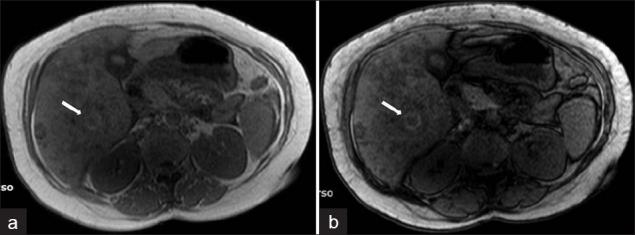

Fascioliasis refers to a zoonosis caused by Fasciola hepatica, a trematode infecting herbivores, but also occurs in humans who ingest the metacercaria found in fresh water plants. Infection in humans is common in developing countries and is also not uncommon in Europe. Diagnosis of this infection is difficult, as the history and symptoms are nonspecific and stool analysis for eggs is negative until the disease is in an advanced state by when the parasite has reached the biliary system. The clinical course consists of two phases; first a hepatic parenchymal phase in which immature larvae invade the liver parenchyma, followed by a ductal phase characterized by the excretion of larvae into the bile ducts. Parenchymal Phase: Ultrasonography (US) findings are nonspecific in this early phase. Computerized tomography (CT) may demonstrate subcapsular low attenuation regions in the liver. Magnetic Resonance imaging (MRI) can also be utilized to establish liver parenchymal involvement, and is better than CT in characterizing hemorrhagic lesions, as well as identifying more lesions relative to CT. Ductal Phase: US examination is most useful at this stage, with its ability to demonstrate the live movement of the worms within the dilated ducts. A CT demonstrates dilated central biliary ducts with periportal tracking, whereas, mild ductal dilatation is poorly appreciated under MRI. Therefore, familiarity with the multimodality imaging features of fascioliasis, in combination with an available confirmatory enzyme-linked immunoassay, would be most helpful for early diagnosis.

肝片吸虫病是一种由肝片吸虫引起的人畜共患病,这种吸虫感染食草动物,但人类摄入淡水植物中的囊蚴后也会感染。在发展中国家,人类感染这种疾病很常见,在欧洲也并不罕见。这种感染的诊断很困难,因为病史和症状不具有特异性,而且在疾病发展到晚期寄生虫进入胆道系统之前,粪便虫卵分析一直呈阴性。临床病程包括两个阶段:首先是肝实质期,未成熟幼虫侵入肝实质,随后是导管期,其特征是幼虫排入胆管。实质期:在此早期阶段,超声检查(US)结果不具有特异性。计算机断层扫描(CT)可能显示肝脏包膜下低密度区域。磁共振成像(MRI)也可用于确定肝实质受累情况,在表征出血性病变以及相对于CT识别更多病变方面比CT更好。导管期:US检查在这个阶段最有用,它能够显示扩张胆管内虫体的活动。CT显示中央胆管扩张并伴有门静脉周围条索状影,而在MRI下轻度胆管扩张不易被察觉。因此,熟悉肝片吸虫病的多模态影像学特征,并结合可用的确诊酶联免疫测定,对早期诊断最有帮助。